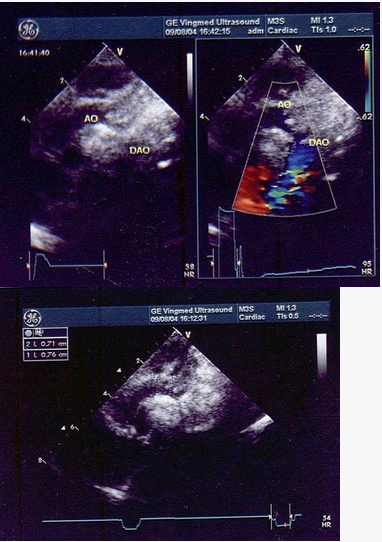

2、超声成像技术的突破:随着技术的进步,三维超声成像、四维超声成像等新技术不断涌现,大大提高了医疗诊断的准确性和效率。